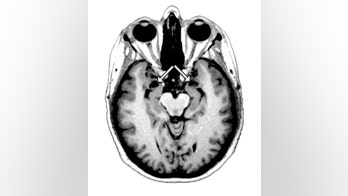

October 28, 2015 Spiders, Snakes? Brain-Damaged Woman Knows No Fear Meet SM, a 44-year-old woman who literally knows no fear. The mother of three has a specific psychological impairment, the result of a very rare genetic disease that damaged a brain structure called the amygdala, which plays a key role in making people feel afraid in threatening situationsÂ